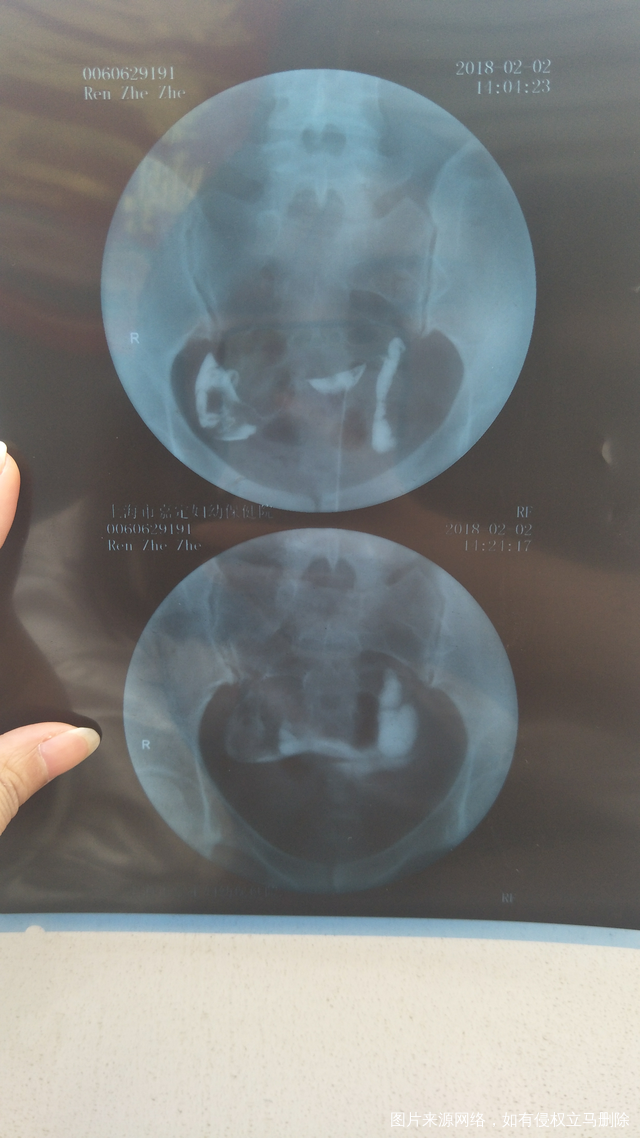

帮忙看下造影片,凑字凑字凑字